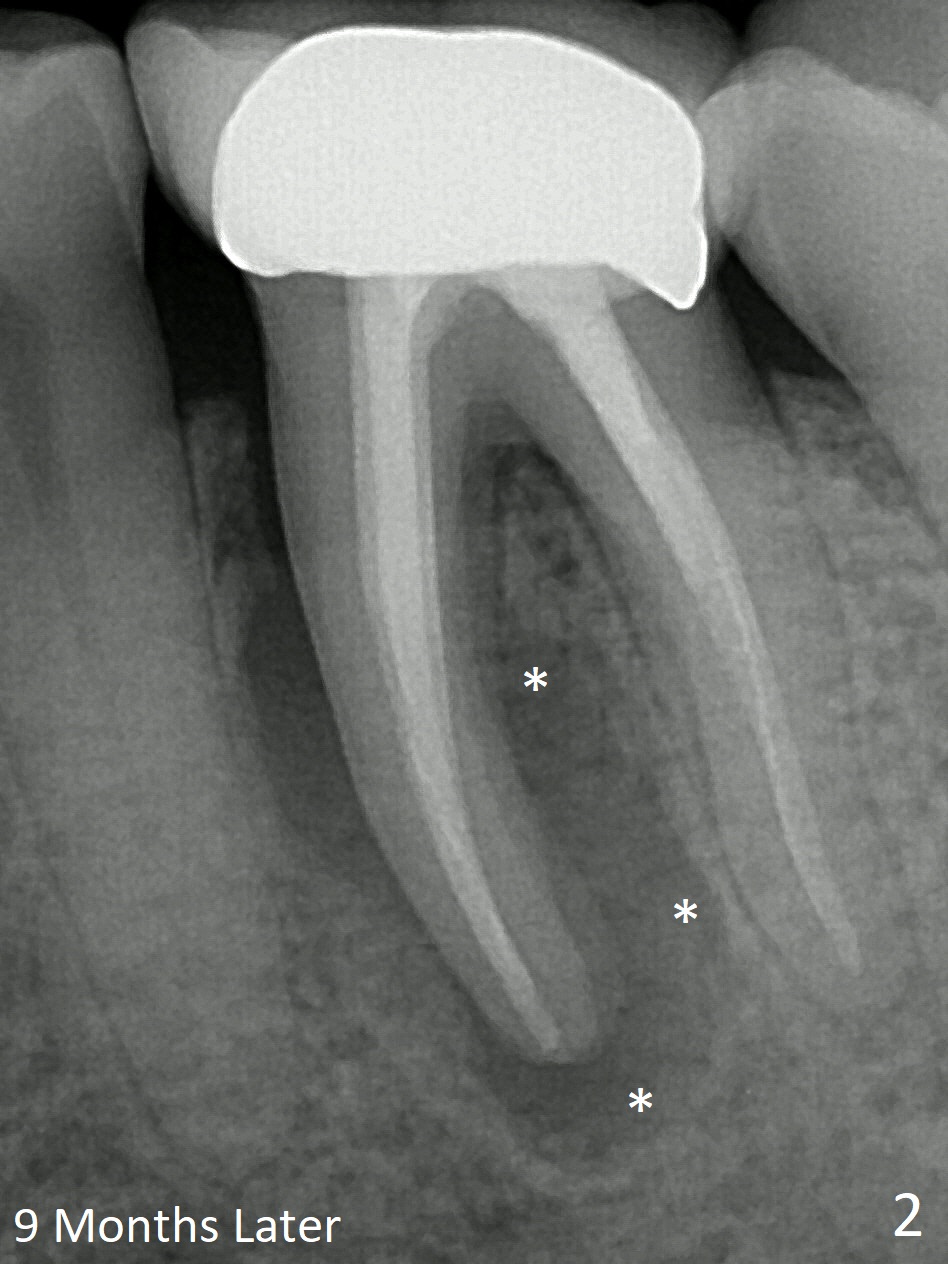

In 9 months more septal bone is lost (Fig.2 *, as compared to Fig.3).